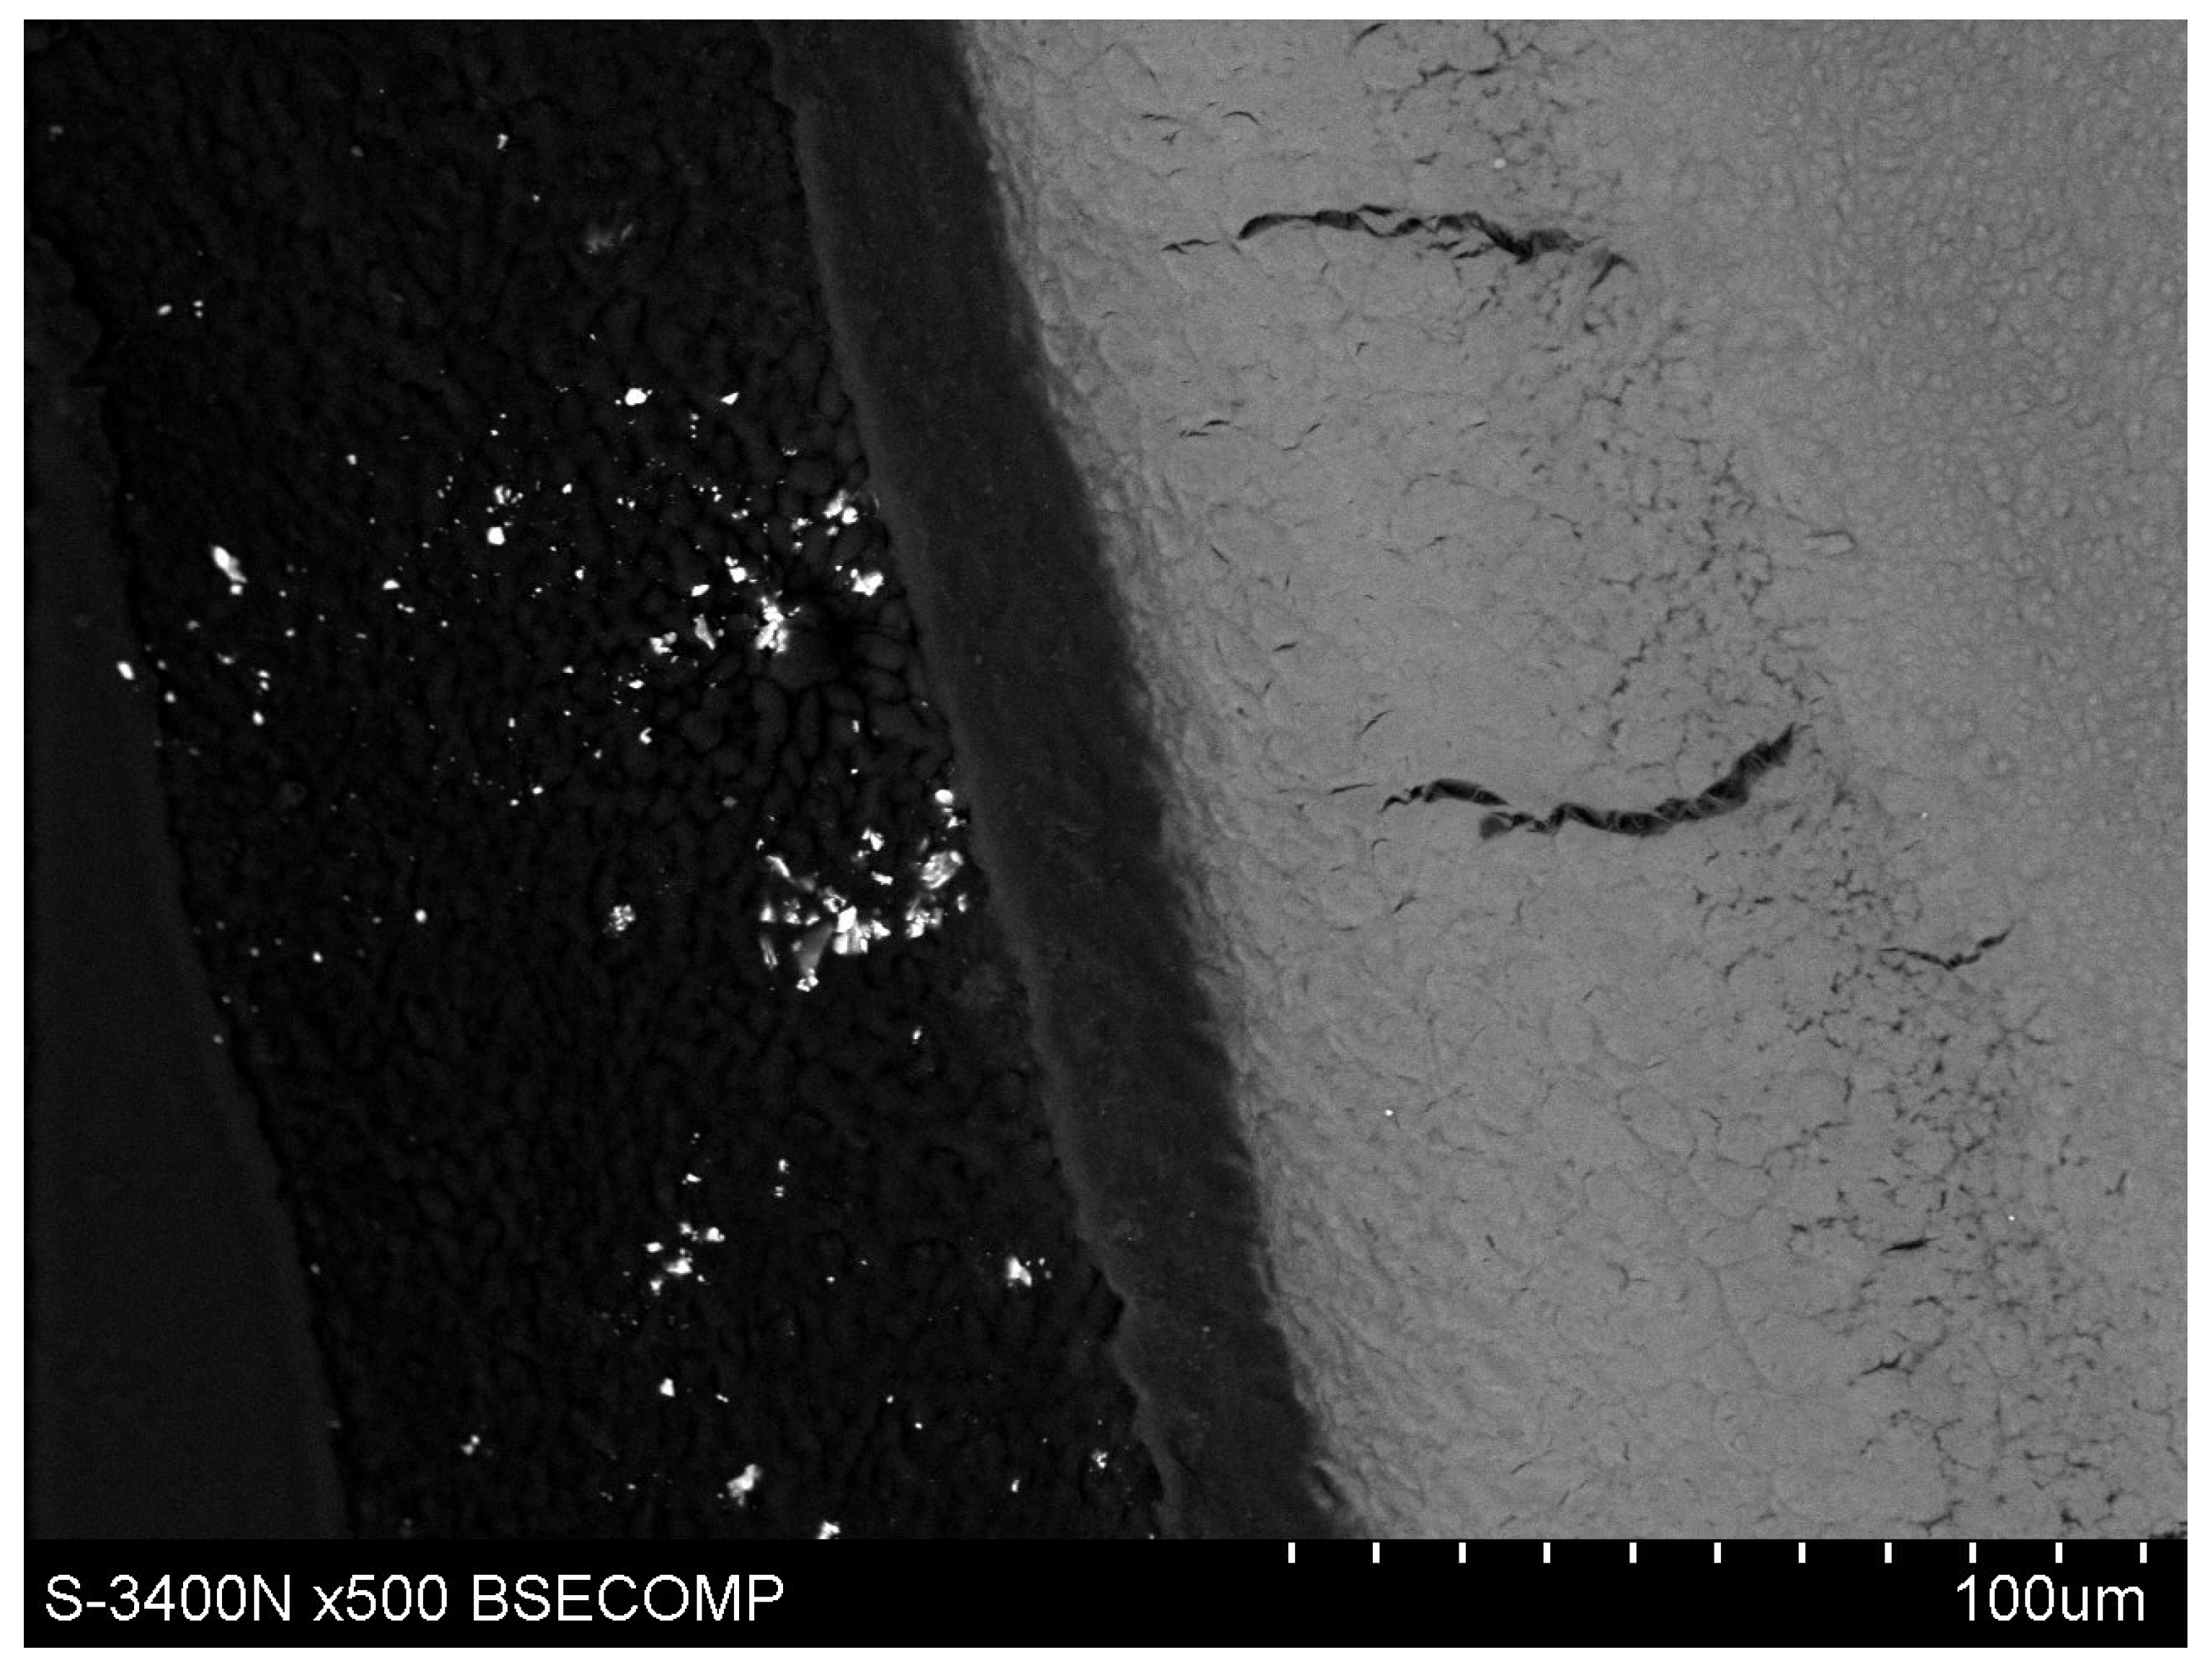

However, microscopic observations showed that yttrium fluoride particles virtually do not penetrate deep into the root cementum—this is mainly due to the particle size of YF3. The used tracer in the form of yttrium trifluoride agglomerates in most cases and remains in the form of conglomerates on the surface of the root cement. Single yttrium trifluoride particles can be seen to arise through the cementum tissues into the root dentin structure.

The study also showed that yttrium fluoride may have insufficient adhesion to the outer surface of tooth root cementum. Longitudinal sections of the teeth made after embedding them in resin showed large amounts of yttrium fluoride particles in the resin used to inlay specimens, sporadically on the surface of root cementum and deep into the cementum and dentin tissue of the root (Figure 5). This demonstrates high affinity of the yttrium fluoride preparation to the used resin (after completion of the crosslinking process, the resin shrinks slightly, forming a gap between the surface of root cementum and resin—Figure 6).

Observations of cementum and root dentin tissue infiltration—resin tissue infiltration is visible to a depth of about 80–120 μm without the use of a tracer, which due to agglomeration and particle size remained on the cementum surface or in the resin used for inlaying (Figure 7, Figure 8, Figure 9, Figure 10 and Figure 11).

Figure 8. Polished section from the study group, experimental preparation + 4% YF3, visible infiltration of root dentin to 80–100 μm, visible large YF3 particle agglomerates in the inlaying resin.

Figure 9. Polished section from the study group, Icon + 4% YF3, visible infiltration of the preparation to 100 μm of root dentin and large YF3 particle agglomerates in the inlaying resin.

Figure 11. Polished section from the study group, experimental preparation + 4% YF3, visible single particles in cementum tissue and numerous YF3 agglomerates in the inlaying resin.